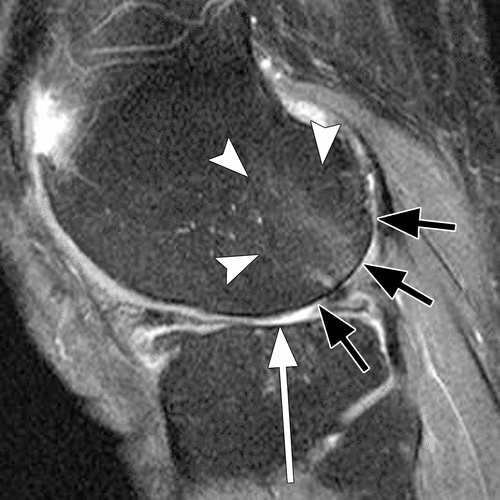

На Т2-взвешенных изображениях визуализируются гиперинтенсивные участки субхондрального костного мозга, соответствующие отёку и реактивным изменениям.

В режиме с подавлением сигнала от жира подчёркивается гиперинтенсивность синовиальной оболочки и мягких тканей, что облегчает выявление синовита и отека параартикулярных тканей.

В режиме с подавлением сигнала от воды определяется истончение суставного хряща с нарушением его однородности, что даёт возможность оценить стадию гонартроза.

В режиме контрастного усиления выявляется усиление сигнала от воспалённой синовиальной оболочки, что уточняет степень активности воспалительного процесса.

- Степень воспалительных изменений в синовиальной оболочке определяется по интенсивности сигнала, что даёт представление об активности воспаления.

- Объём суставного выпота измеряется по площади и распределению жидкости в полости сустава, что важно для оценки выраженности воспалительного компонента.